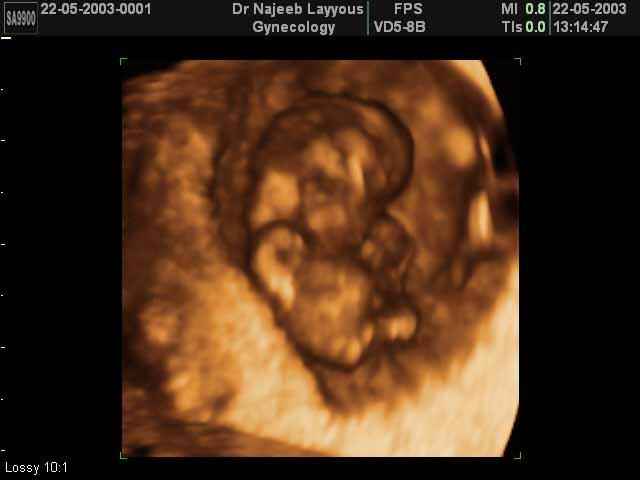

- First Trimester Ultrasound Photos

3D First Trimester Ultrasound Scan Photos ( Early Pregnancy Ultrasound Photos ) | Dr N Layyous